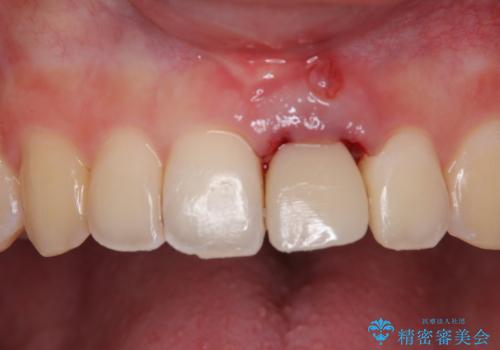

長い間歯肉が炎症を患っていたため、炎症改善後には歯肉がやや退縮した状態となっていました。

歯肉移植により歯肉形態を改善するプランも提案しましたが、十分な仕上がりとのことで、大変満足していただけました。